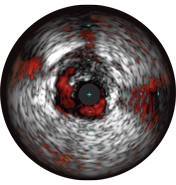

На мальаппозицию указывает наличие крови за стратами стента. При визуализации с использованием режима ChromaFlo кровоток окрашен в красный цвет для простого выявления мальаппозиции и других особенностей просвета.

• Простая оценка аппозиции стента, размера просвета и других показателей за счет выделения кровотока красным цветом одним нажатием кнопки.